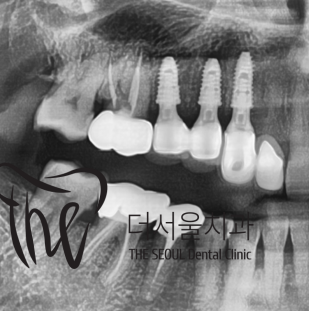

그것도, 원래 있었던 치아마냥 똑같이

재현을 해드리면서 시술 종료!

결국 당일 시술 후 즉시식립을 진행하게 되었네요.

치료기간은 대략 3개월만에 끝내드렸던 걸로

기억을 하고 있습니다.